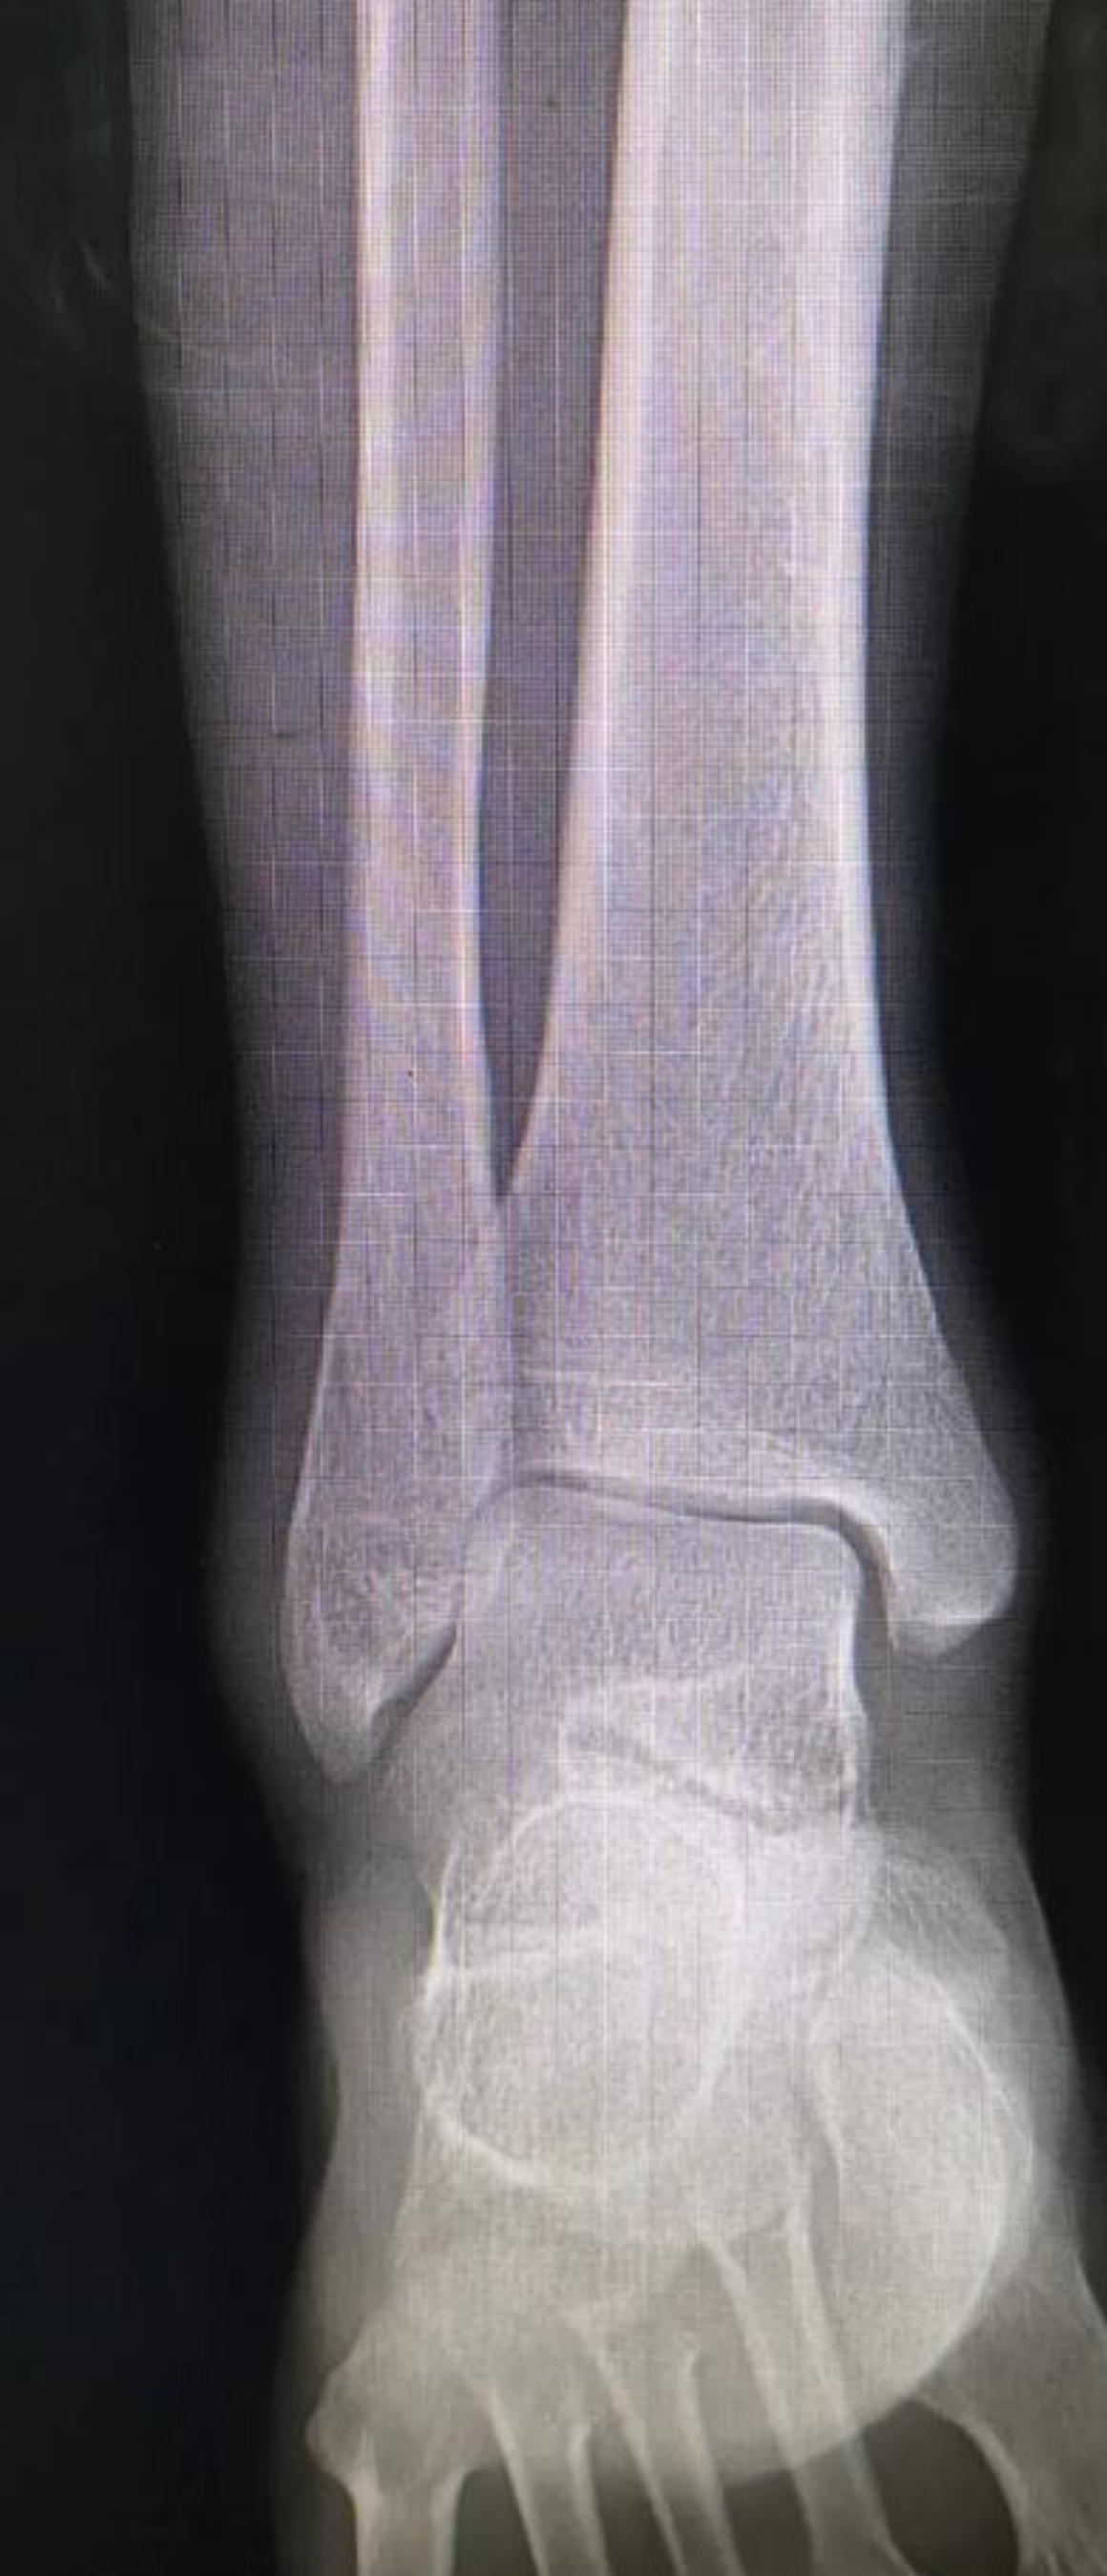

医生会通过问诊、体格检查(如“抽屉试验”)判断韧带损伤程度,必要时借助X光排除骨折,或通过MRI明确韧带撕裂情况。严重者(如III级断裂、合并骨折)可能需石膏固定甚至手术治疗。